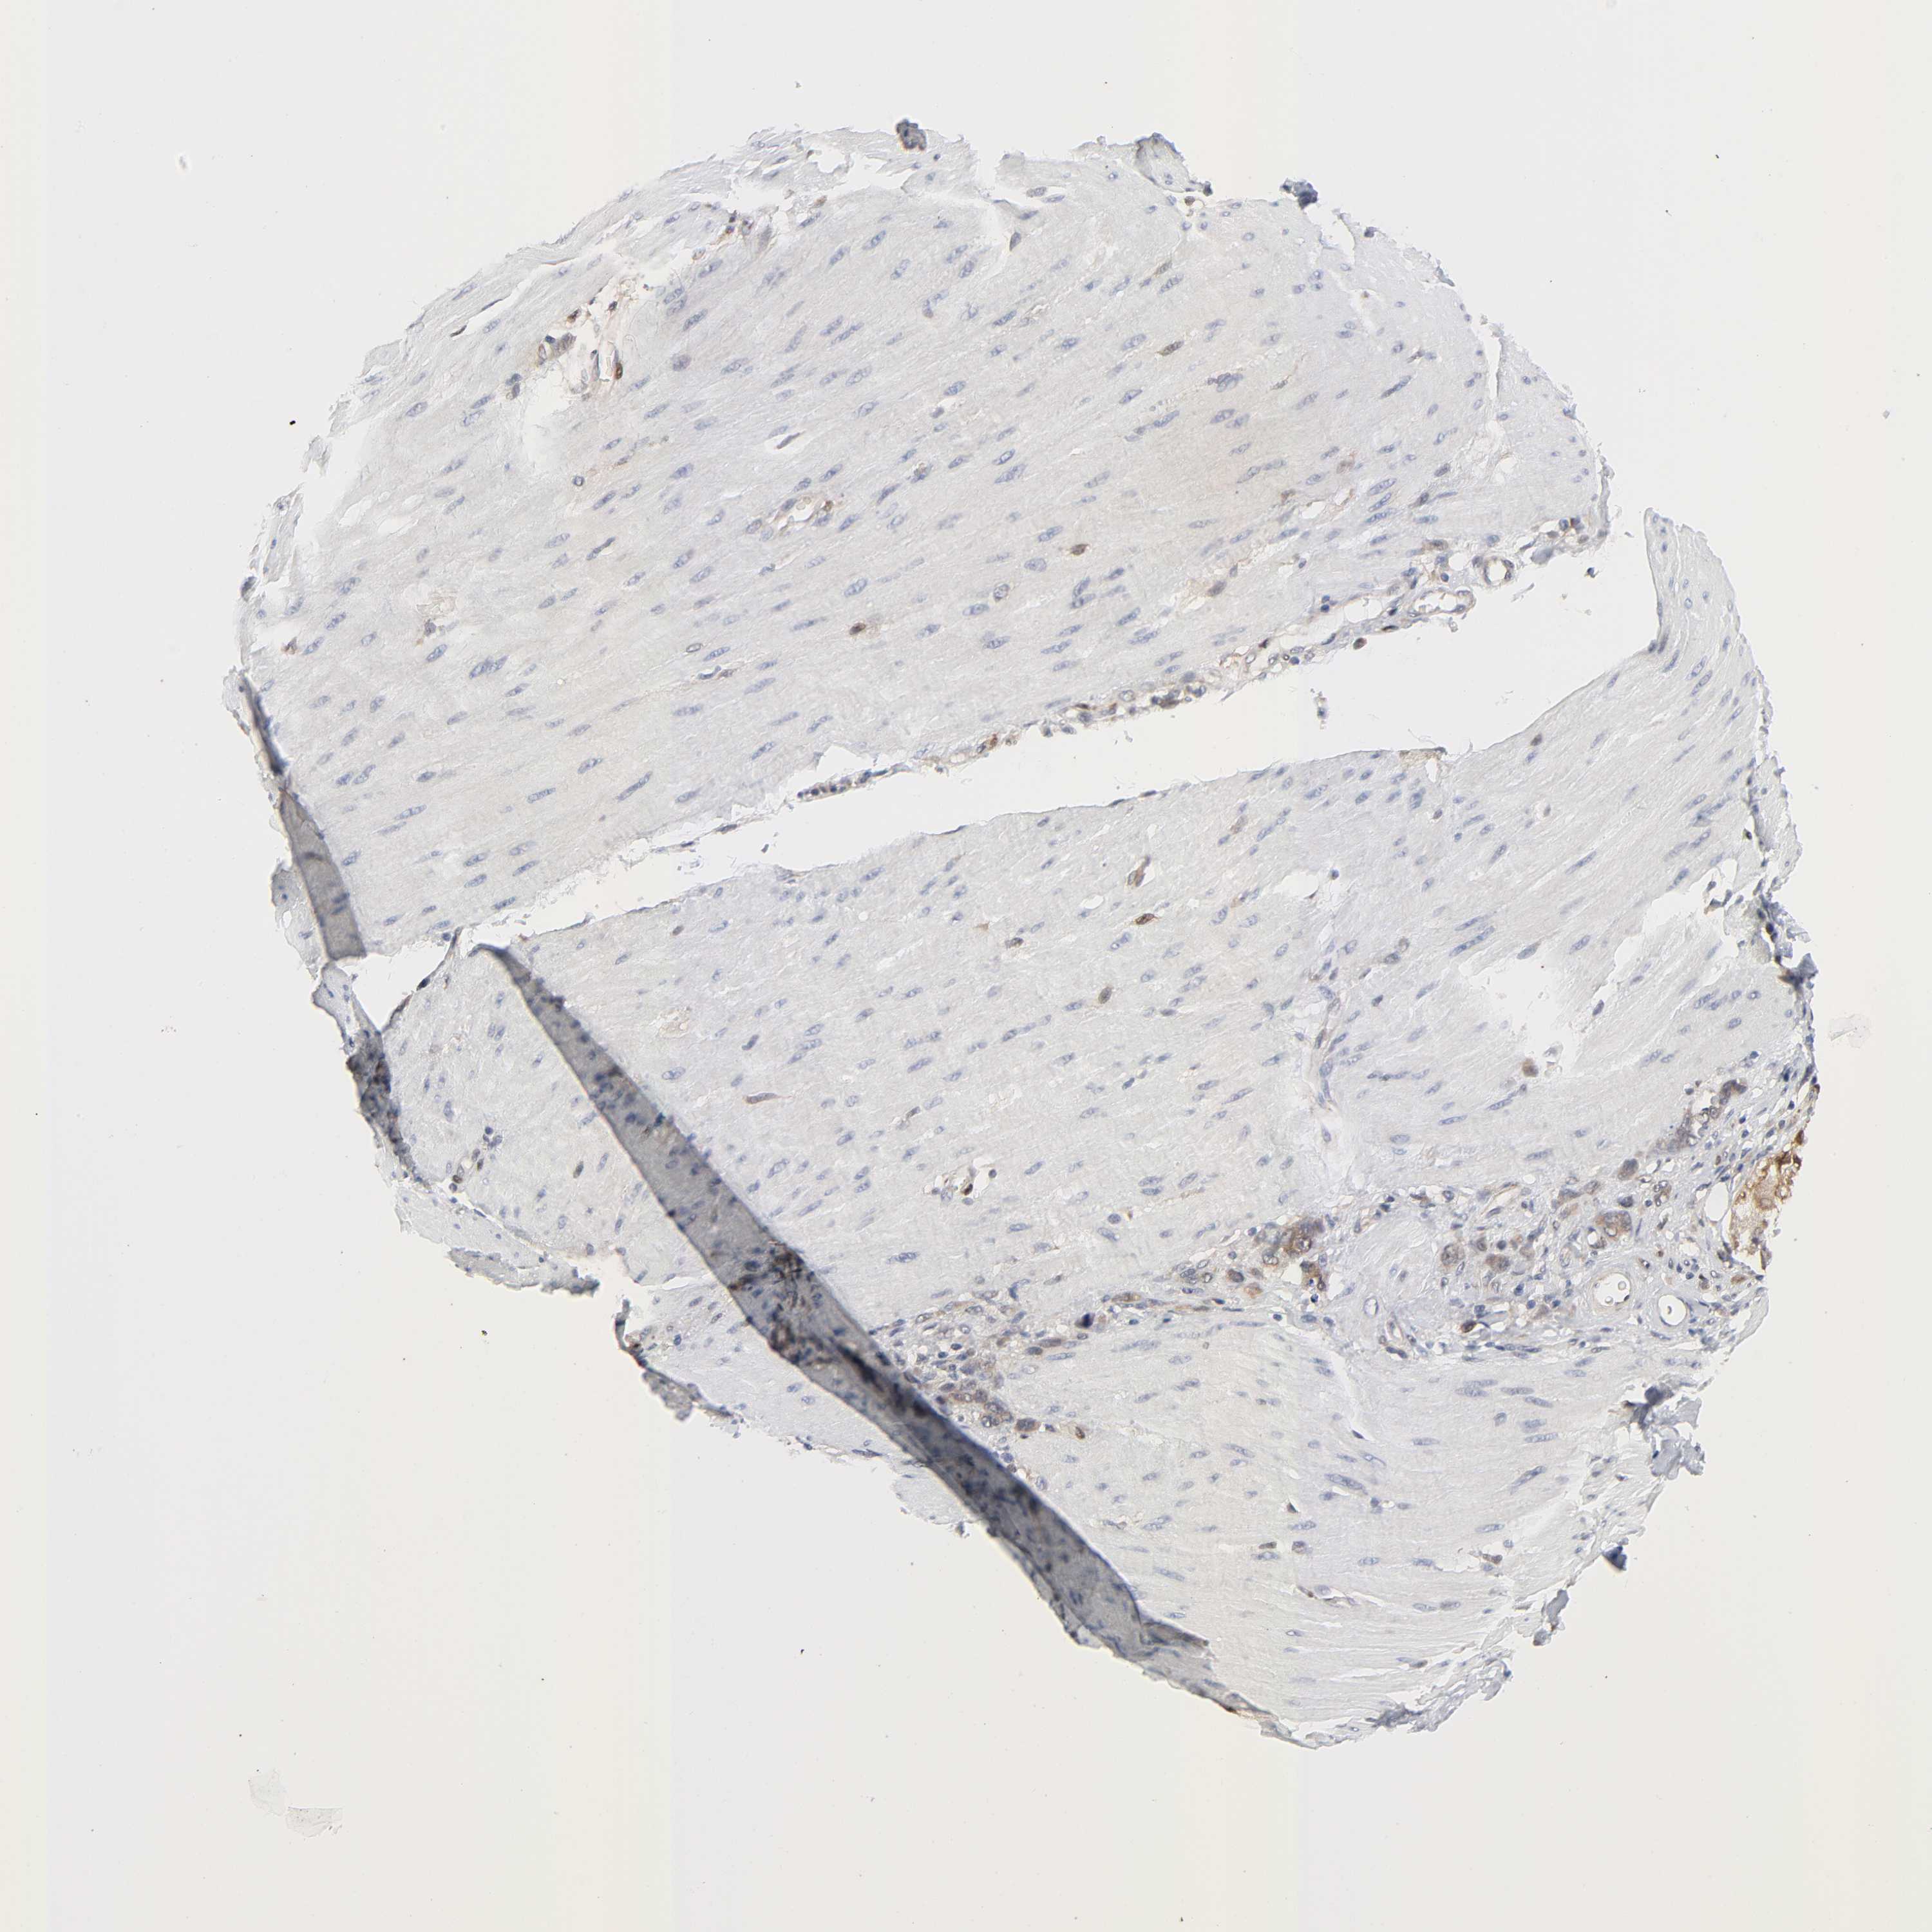

STOMACH CANCER - Protein expressioni

A mouse-over function shows sample information and annotation data. Click on an image to view it in a full screen mode. Samples can be filtered based on level of antibody staining by selecting one or several of the following categories: high, medium, low and not detected. The assay and annotation is described here.

Note that samples used for immunohistochemistry by the Human Protein Atlas do not correspond to samples in the TCGA dataset.

Antibody stainingi

Antibody staining in the annotated cell types in the current human tissue is reported as not detected, low, medium, or high, based on conventional immunohistochemistry profiling in selected tissues. This score is based on the combination of the staining intensity and fraction of stained cells.

Each image is clickable and will lead to virtual microscopy that enables deeper exploration of all samples and also displays staining intensity scores, fraction scores and subcellular localization as well as patient and tissue information for each sample.

Antibody HPA031335

Antibody CAB004076

Antibody CAB080153

Antibody CAB080157

Staining

High

Medium

Low

Not detected

Intensity

Strong

Moderate

Weak

Negative

Quantity

>75%

75%-25%

<25%

None

Location

Nuclear

Cytoplasmic/membranous

Cytoplasmic/membranous,nuclear

Adenocarcinoma, NOS

Adenocarcinoma, High grade